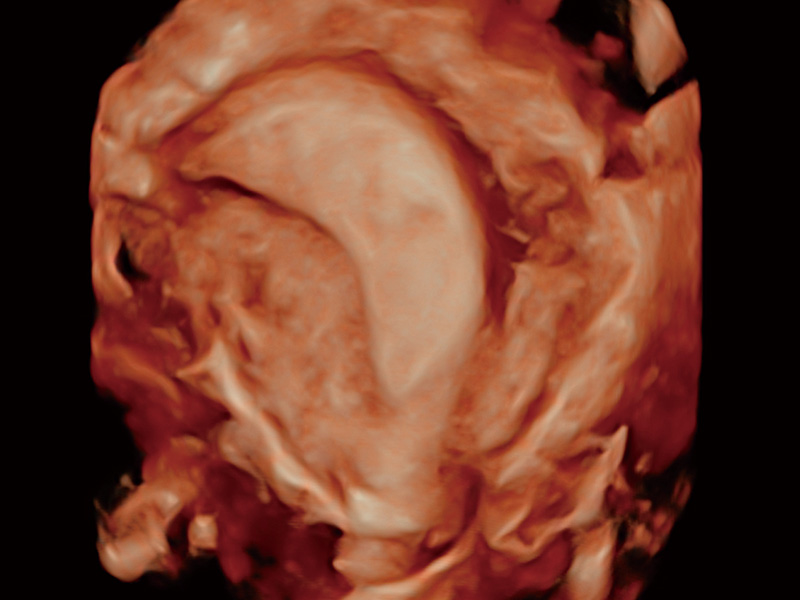

腔内容积探头

腔内三维成像技术获得显著提升,超大扇角在满足日常基础扫查的同时,支持卵泡自动测量及多种三维渲染模式,为您提供更多的诊断信息,尤其是在子宫畸形的诊断,内膜及肿瘤占位观测中起到了重要的作用。

卵巢多囊样改变